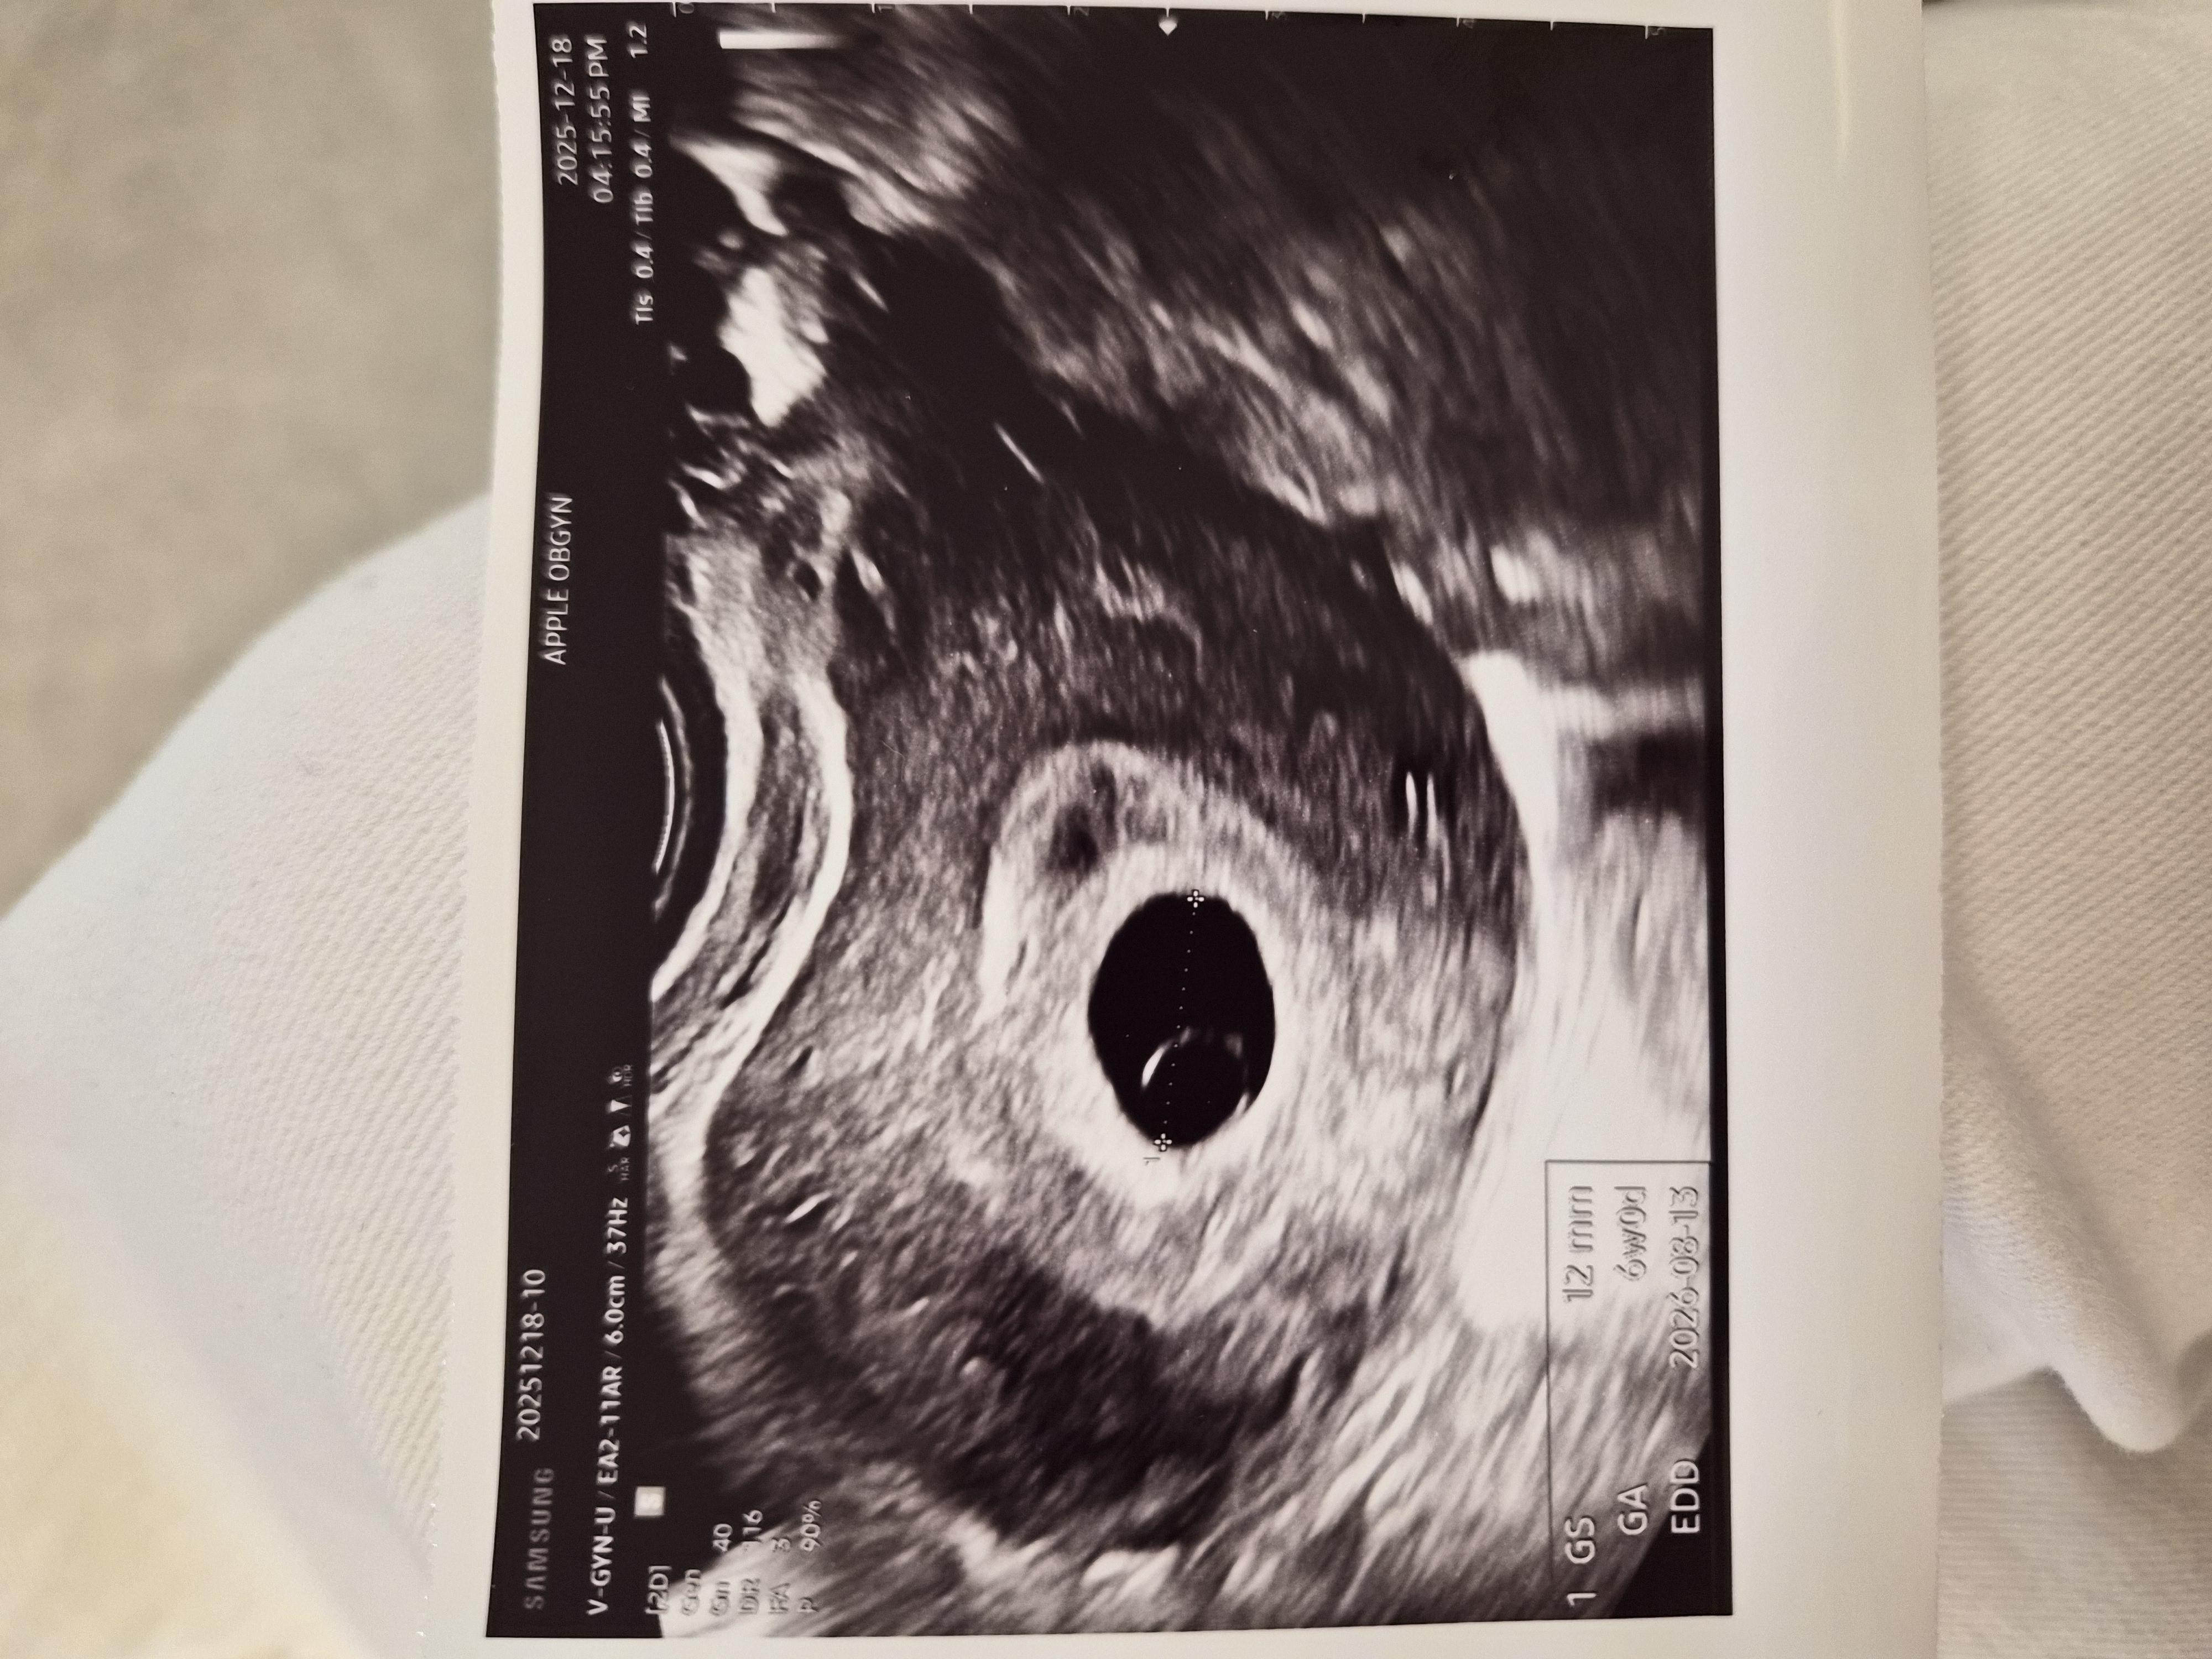

초음파 사진 한번 봐주세요!

6주 0일차 서브병원에서 보고 온 초음파인데 난황이 좀 크다고 다음주에 심소 들으면 괜찮다고 하는데 걱정이 되서요.. 다른 베동님들 보시기엔 어떠신지 궁금해서 올려봅니다ㅠㅠ